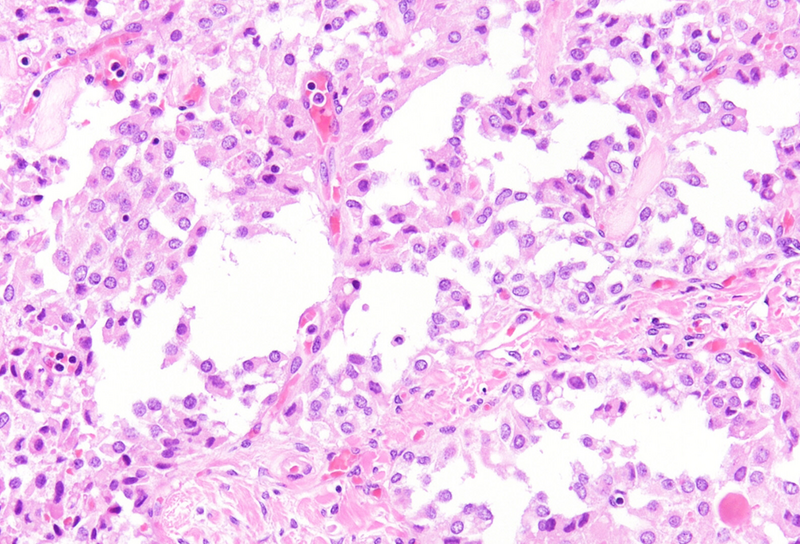

Histological examination revealed a well-circumscribed neoplasm with a fibrous capsule (Panel A), composed of uniform, poorly cohesive cells arranged in both solid (Panel B) and pseudopapillary structures (Panel C). The pseudopapillae resulted from degenerative changes leading to detachment of tumor cells from another and from central fibrovascular cores. Stromal hyalinization was also noted (Panel D). The neoplastic cells were monomorphic, with round to oval nuclei showing finely dispersed chromatin, inconspicuous nucleoli, and moderate amounts of eosinophilic to clear cytoplasm. Mitoses were not seen.